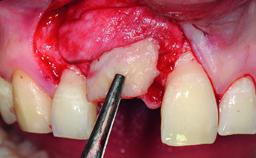

A 30-year-old patient presented at our clinic with a chief complaint of pain in her endodontically treated right maxillary central incisor (tooth 11) with a post-and-core and a fixed single crown. She had a very high lip line, a medium to thin soft-tissue phenotype, and a medium scalloped gingival contour. She also had high esthetic expectations because of her young age and beautiful smile. However, her expectations were realistic and she understood the risks of the treatment. At the initial clinical examination there was a slight mobility of tooth 11; no fistula was observed. The patient also had a single crown on the adjacent tooth 21. Both restorations were old and esthetically deficient. A digital periapical radiograph showed a very small periapical radiolucency, a thick intraradicular post, and no separation between root fragments.

Bone Augmentation Staged

Augmentation Materials Xenogenous|Membrane

Soft Tissue Grafting Simultaneous